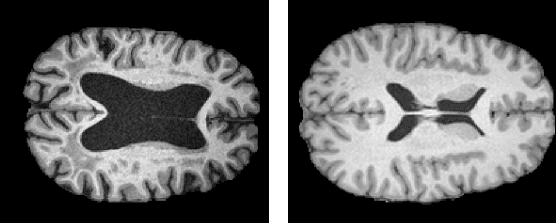

Abstract:The detection of lesions in magnetic resonance imaging (MRI)-scans of human brains remains challenging, time-consuming and error-prone. Recently, unsupervised anomaly detection (UAD) methods have shown promising results for this task. These methods rely on training data sets that solely contain healthy samples. Compared to supervised approaches, this significantly reduces the need for an extensive amount of labeled training data. However, data labelling remains error-prone. We study how unhealthy samples within the training data affect anomaly detection performance for brain MRI-scans. For our evaluations, we consider three publicly available data sets and use autoencoders (AE) as a well-established baseline method for UAD. We systematically evaluate the effect of impured training data by injecting different quantities of unhealthy samples to our training set of healthy samples from T1-weighted MRI-scans. We evaluate a method to identify falsely labeled samples directly during training based on the reconstruction error of the AE. Our results show that training with impured data decreases the UAD performance notably even with few falsely labeled samples. By performing outlier removal directly during training based on the reconstruction-loss, we demonstrate that falsely labeled data can be detected and removed to mitigate the effect of falsely labeled data. Overall, we highlight the importance of clean data sets for UAD in brain MRI and demonstrate an approach for detecting falsely labeled data directly during training.

Abstract:Lesion detection in brain Magnetic Resonance Images (MRIs) remains a challenging task. MRIs are typically read and interpreted by domain experts, which is a tedious and time-consuming process. Recently, unsupervised anomaly detection (UAD) in brain MRI with deep learning has shown promising results to provide a quick, initial assessment. So far, these methods only rely on the visual appearance of healthy brain anatomy for anomaly detection. Another biomarker for abnormal brain development is the deviation between the brain age and the chronological age, which is unexplored in combination with UAD. We propose deep learning for UAD in 3D brain MRI considering additional age information. We analyze the value of age information during training, as an additional anomaly score, and systematically study several architecture concepts. Based on our analysis, we propose a novel deep learning approach for UAD with multi-task age prediction. We use clinical T1-weighted MRIs of 1735 healthy subjects and the publicly available BraTs 2019 data set for our study. Our novel approach significantly improves UAD performance with an AUC of 92.60% compared to an AUC-score of 84.37% using previous approaches without age information.

Abstract:Purpose. Brain Magnetic Resonance Images (MRIs) are essential for the diagnosis of neurological diseases. Recently, deep learning methods for unsupervised anomaly detection (UAD) have been proposed for the analysis of brain MRI. These methods rely on healthy brain MRIs and eliminate the requirement of pixel-wise annotated data compared to supervised deep learning. While a wide range of methods for UAD have been proposed, these methods are mostly 2D and only learn from MRI slices, disregarding that brain lesions are inherently 3D and the spatial context of MRI volumes remains unexploited. Methods. We investigate whether using increased spatial context by using MRI volumes combined with spatial erasing leads to improved unsupervised anomaly segmentation performance compared to learning from slices. We evaluate and compare 2D variational autoencoder (VAE) to their 3D counterpart, propose 3D input erasing, and systemically study the impact of the data set size on the performance. Results. Using two publicly available segmentation data sets for evaluation, 3D VAE outperform their 2D counterpart, highlighting the advantage of volumetric context. Also, our 3D erasing methods allow for further performance improvements. Our best performing 3D VAE with input erasing leads to an average DICE score of 31.40% compared to 25.76% for the 2D VAE. Conclusions. We propose 3D deep learning methods for UAD in brain MRI combined with 3D erasing and demonstrate that 3D methods clearly outperform their 2D counterpart for anomaly segmentation. Also, our spatial erasing method allows for further performance improvements and reduces the requirement for large data sets.